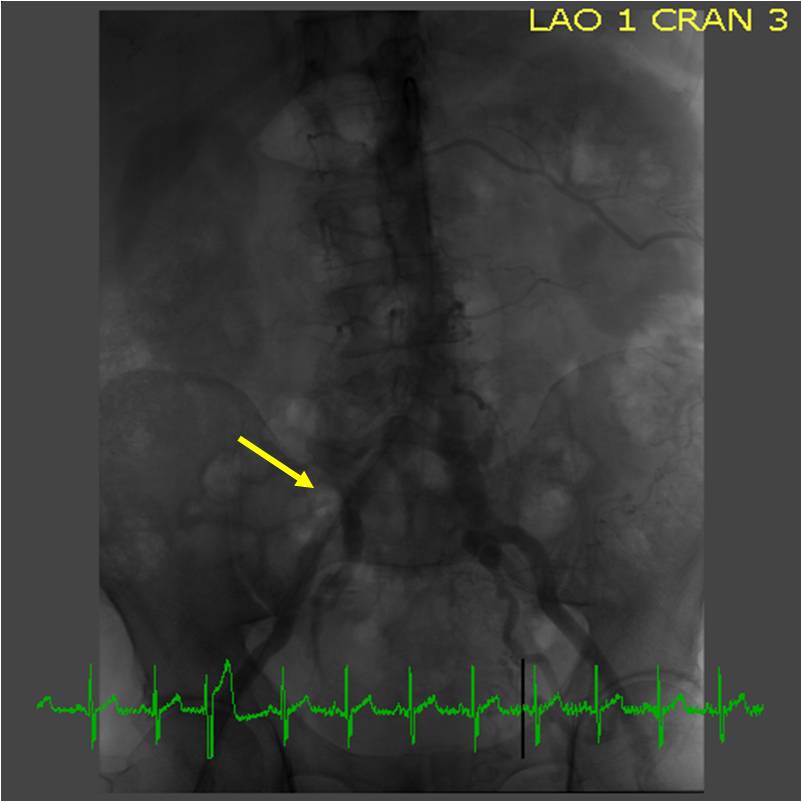

You perform an angiogram on a 64 year-old man with lifestyle-limiting claudication. An eccentric, calcified 60{8ceaa46882e4d49283ff23b35262537230ad541262f55a031ead545e66522058} stenosis originating in the right common iliac and extending to the right external iliac artery is identified.

There is an associated 40 mm Hg pressure gradient across this lesion. You successfully cross the lesion in retrograde fashion from right femoral artery access. You then perform balloon angioplasty with good results yielding a 20{8ceaa46882e4d49283ff23b35262537230ad541262f55a031ead545e66522058} residual stenosis, no evidence of dissection, and no evidence of distal embolization. Should stenting be performed, and if so, what type of stent should be selected?

For the patient in the vignette, a balloon-expandable bare metal stent was successfully deployed across the treated segment with excellent angiographic results.

The selection of a bare metal stent avoided jeopardizing the ipsilateral internal iliac artery. Since the lesion did not encroach upon the distal external iliac-common femoral artery junction, a compelling indication for a self-expanding stent was not present. Fortunately, the patient’s claudication symptoms resolved, and he is clinically well 6 months later.